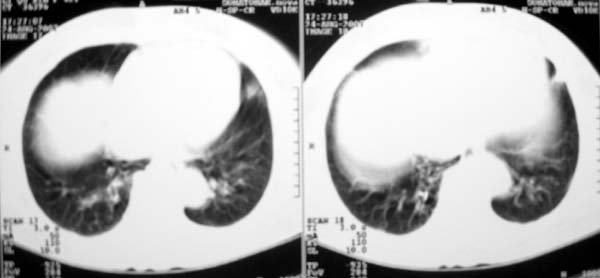

以下是引用zjzjr在2007-8-30 22:22:00的发言:[br]右上肺肺囊肿合并感染.右下肺肺大泡.左肺舌段感染.

以下是引用天南地北在2007-8-30 23:19:00的发言:[br][quote]以下是引用zjzjr在2007-8-30 22:22:00的发言:[br]右上肺肺囊肿合并感染.右下肺肺大泡.左肺舌段感染.